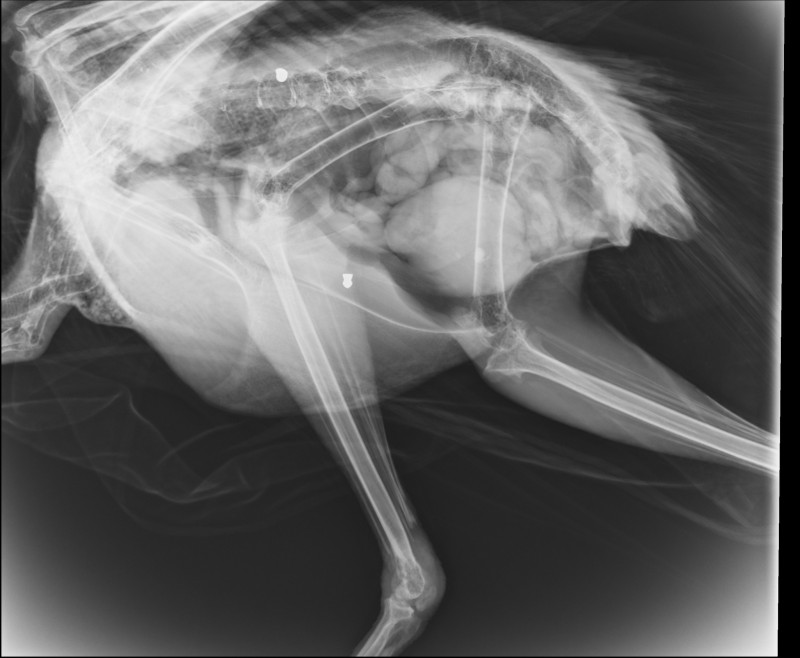

Το εντυπωσιακό πτηνό κούτσαινε το τελευταίο διάστημα και οι ακτινογραφίες «έδειξαν» ότι μέσα στο σώμα του υπήρχαν δυο βολίδες αεροβόλου και ένα σκάγι

Το παγώνι φέρεται να δέχθηκε πυροβολισμούς, γεγονός που επιβεβαίωσαν και σχετικές ακτινογραφίες που «έδειξαν μάλιστα δυο βολίδες αεροβόλου κι ένα σκάγι.